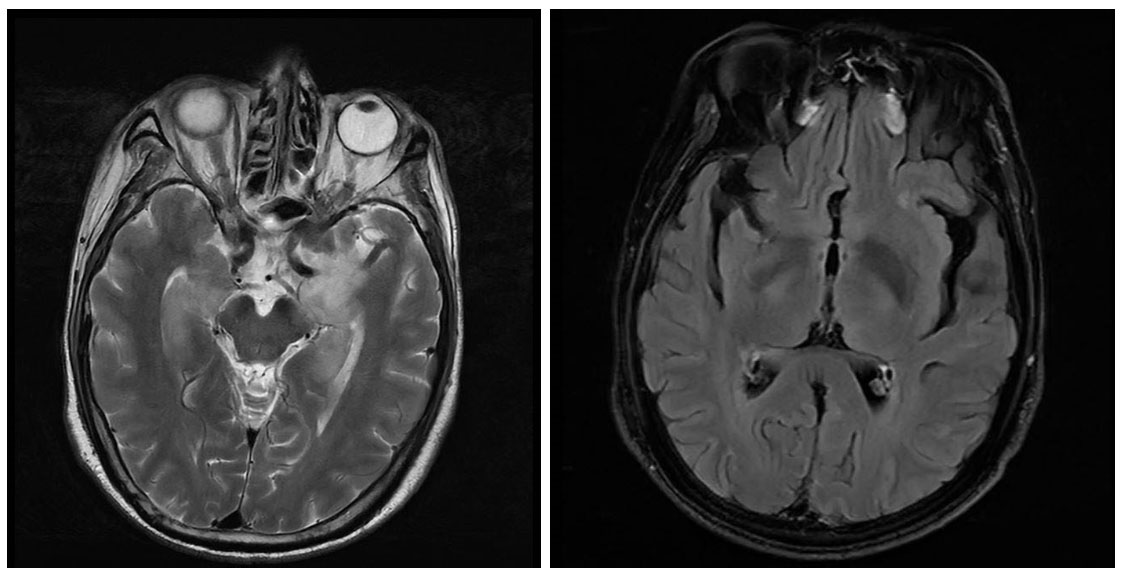

| A为平扫MRI,B为增强MRI 图 3 头颅磁共振影像 |

1.3 治疗及转归入院后予以丙种球蛋白25 g qd(连用5 d)、甲强龙500 mg qd起降阶梯治疗(每3 d减半量); 同时辅以左乙拉西坦片0.5 mg q12 h鼻饲、苯巴比妥钠注射液0.1 g q8 h肌肉注射抗癫痫及其他营养对症处理。后患者病情逐渐稳定转入神经内科专科住院。经抗自免脑治疗后患者心律失常逐渐好转,予以摘除临时起搏器,并进一步行颅脑MRI及增强MRI检查,颅脑MRI(2021-11-10)提示:两侧额顶叶、左侧颞叶皮层下和两侧半卵圆中心见多发斑点状T1WI低、T2WI高信号,T2 Flair高信号,脑室脑沟脑池未见明显异常,中线结构居中。颅脑增强MRI提示:两侧颞叶、岛叶、额叶多发片状T2WI高信号影,T2 Flair高信号,DWI呈稍高信号,以额叶为主,两侧额顶颞叶、脑室周围、半卵圆区、基底节区多发点片状长T2高信号,黑水像高信号,脑室脑沟脑池未见异常,中线居中。两侧颞叶、岛叶及额叶多发病灶,考虑脑炎:两侧额叶颞叶、脑室周围、半卵圆区、基底节区多发缺血灶(图 3),癫痫治疗方案基本同上。1月后患者转入绍兴市上虞区人民医院行康复治疗,后患者逐渐恢复生活自理能力。半年后(2022-04)随访,患者于浙大一附院诊断为小细胞肺癌(晚期),目前行中药、化疗治疗。